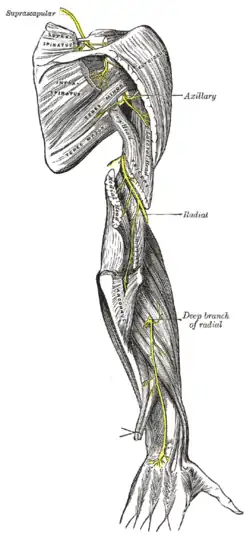

Os nervos supraescapular, axilar e radial.

Os nervos supraescapular, axilar e radial.